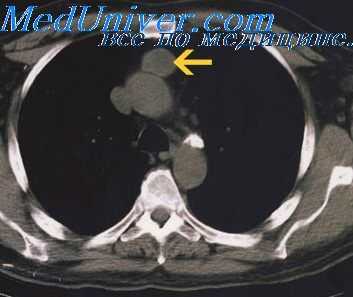

В дальнейшем еще 3 раза через различные интервалы выявляли и удаляли метастатические узлы тимомы различных участков диафрагмальной и костальной плевры справа, все типа B1 (рис. 1): Рис. 1. Тимома тип В1. Гистологическое исследование удаленного метастаза в париетальной плевре, ×40. 1) через 8 лет и 11 мес после первой операции удалены по 2 метастаза в диафрагмальной и париетальной плевре на уровне Х ребра размером от 1 до 5,5 см в диаметре тораколюмбальным доступом. Вокруг опухолей была сформирована тонкая фиброзная капсула; 2) через 9 лет и 1 мес после первой операции с техническими трудностями из-за выраженных плевральных сращений удален метастаз тимомы в диафрагмальной поверхности плевры с сформировавшейся фиброзной капсулой; 3) через 9 лет и 8 мес после первой операции удален метастаз размером 45×18×52 мм (рис. 2), Рис. 2. МСКТ с болюсным контрастным усилением: метастаз тимомы в париетальной плевре на уровне переднего отрезка VIII ребра справа. а — поперечный срез; б — прямая проекция. a — transverse section; b — frontal view. который располагался позади переднего отрезка VIII ребра с врастанием в межреберные мышцы. Метастаз удален без торакотомии и технических трудностей, произвели резекцию небольшого участка VIII ребра справа.

(а) У пациента с тимомой при КТ с контрастным усилением в преваскулярном отделе средостения определяется объемное образование, гетерогенно накапливающее контрастное вещество. Образование расположено в левой половине преваскулярного отдела средостения и прилежит клеточному стволу. Признаки инвазии сосуда отсутствуют. Отсутствие клетчаточных пространств при КТ органов грудной клетки не является надежным признаком местнодеструирующего роста.